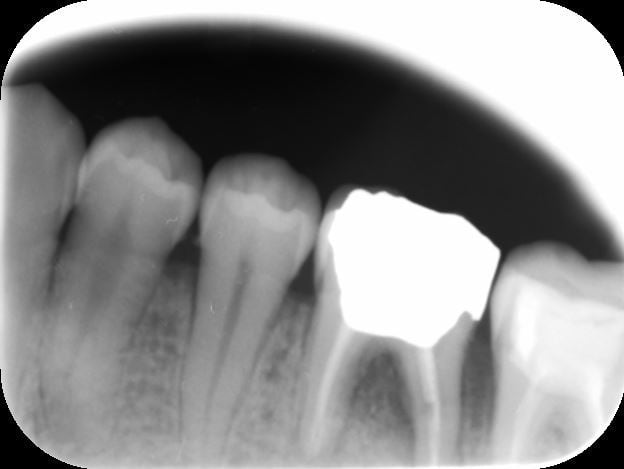

36 wcy3hf - Eugenol

36 photo zz29gy - Eugenol